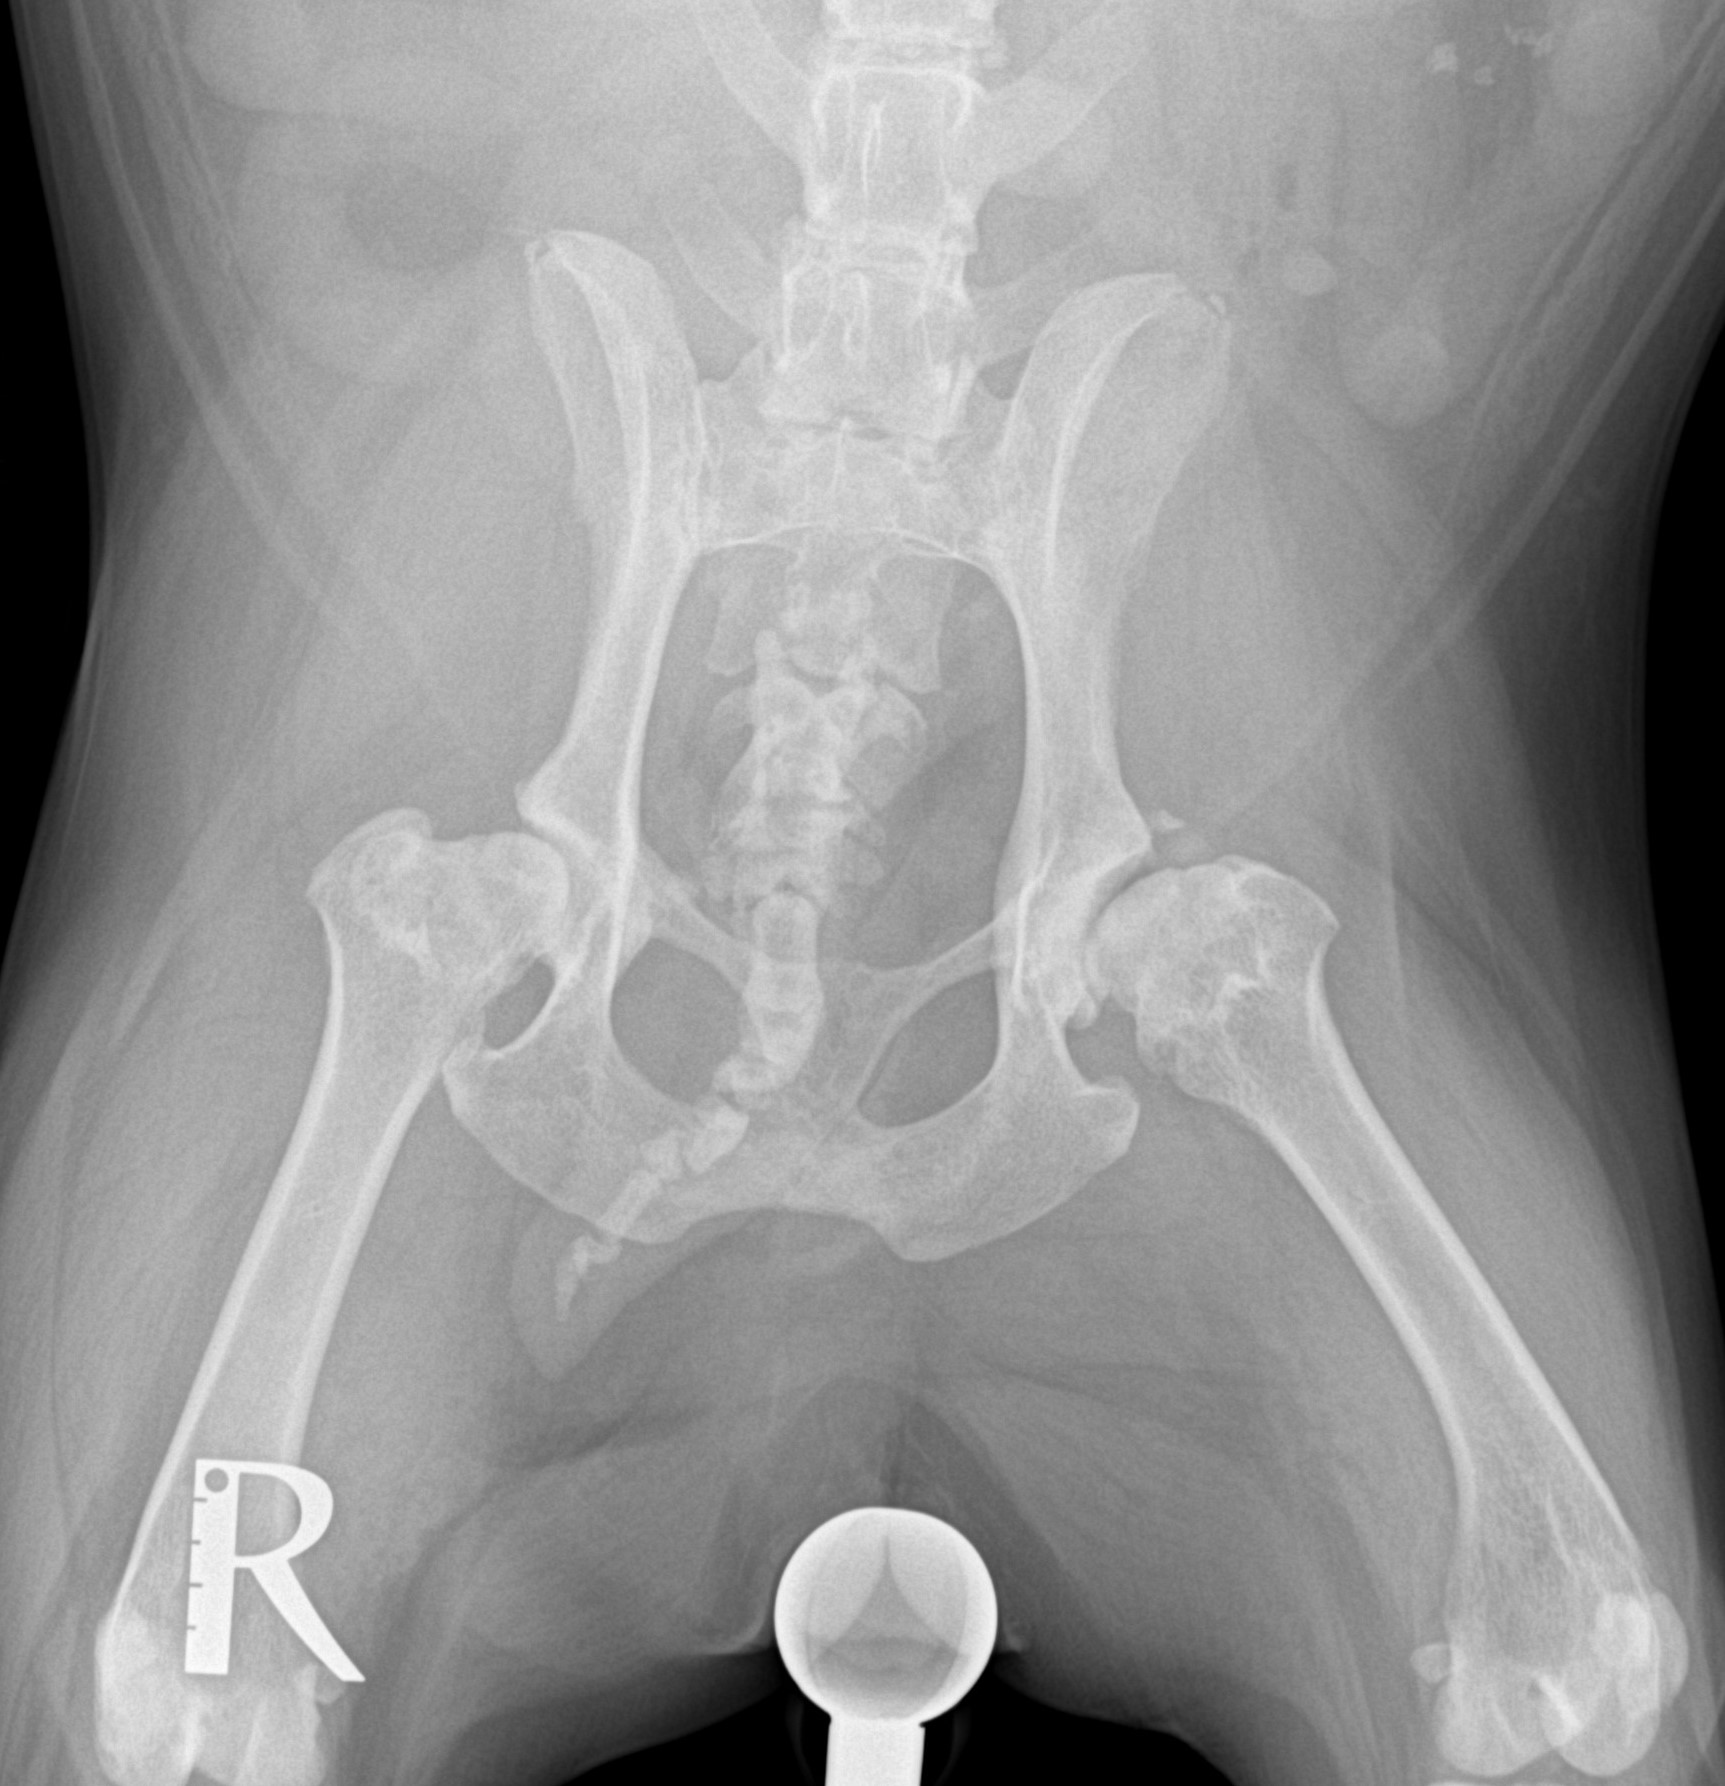

Resekce hlavice stehenní kosti při silné artróze